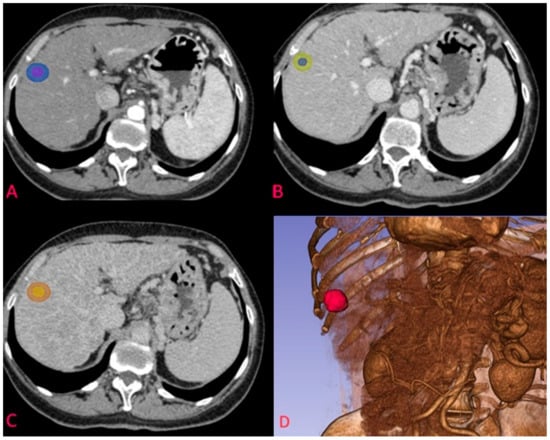

2.4. Image Segmentation